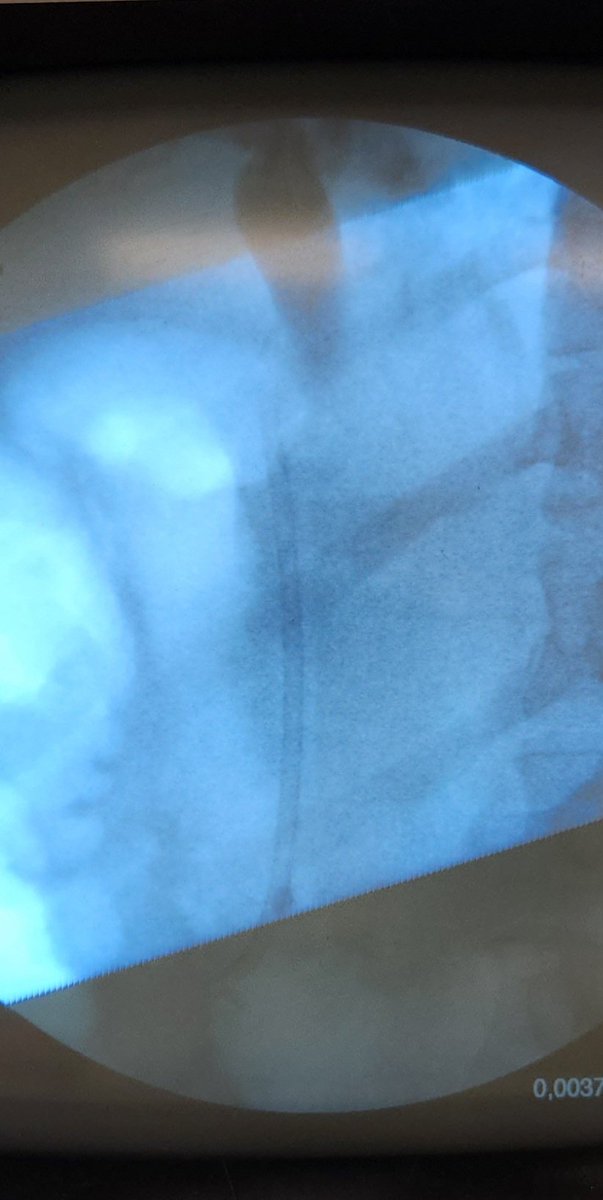

Dilation of the intrahepatic and extrahepatic bile ducts secondary to stone obstruction, diagnosed with POCUS in a patient with fever in the ICU, requiring ERCP and placement of a biliary stent. #POCUS #cholangitis #ICU